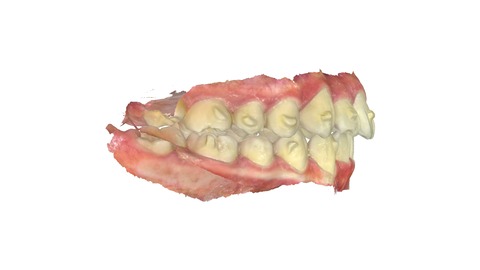

下の歯にも同様に引っ込んだ歯がある。